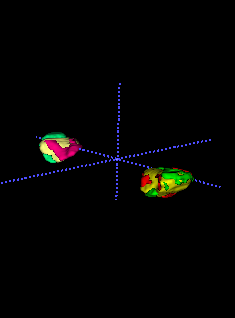

In Chapter 6, we propose an end-to-end, atlas-free 3D convolutional deep learning framework for fast and fully automated whole-volume HaN anatomy segmentation [115]. Our deep learning model, called AnatomyNet, segments OARs from head and neck CT images in an end-to-end fashion, receiving whole-volume HaN CT images as input and generating masks of all OARs of interest in one shot. AnatomyNet is built upon the popular 3D U-net architecture, but extends it in three important ways: 1) a new encoding scheme to allow auto-segmentation on whole-volume CT images instead of local patches or subsets of slices, 2) incorporating 3D squeeze-and-excitation residual blocks in encoding layers for better feature representation, and 3) a new loss function combining Dice scores and focal loss to facilitate the training of the neural model. These features are designed to address two main challenges in deep-learning-based HaN segmentation: a) segmenting small anatomies (i.e., optic chiasm and optic nerves) occupying only a few slices, and b) training with inconsistent data annotations with missing ground truth for some anatomical structures. We collect 261 HaN CT images to train AnatomyNet, and use MICCAI Head and Neck Auto Segmentation Challenge 2015 as a benchmark dataset to evaluate the performance of AnatomyNet. The objective is to segment nine anatomies: brain stem, chiasm, mandible, optic nerve left, optic nerve right, parotid gland left, parotid gland right, submandibular gland left, and submandibular gland right. Compared to previous state-of-the-art results from the MICCAI 2015 competition, AnatomyNet increases Dice similarity coefficient by 3.3% on average. AnatomyNet takes about 0.12 seconds to fully segment a head and neck CT image of dimension , significantly faster than previous methods. In addition, the model is able to process whole-volume CT images and delineate all OARs in one pass, requiring little pre- or post-processing. We demonstrate that our proposed model can improve segmentation accuracy and simplify the auto-segmentation pipeline. These contributions are released as an open-source software package called AnatomyNet, which is publicly available555https://github.com/wentaozhu/AnatomyNet-for-anatomical-segmentation. Portions of this chapter were published as part of [115].